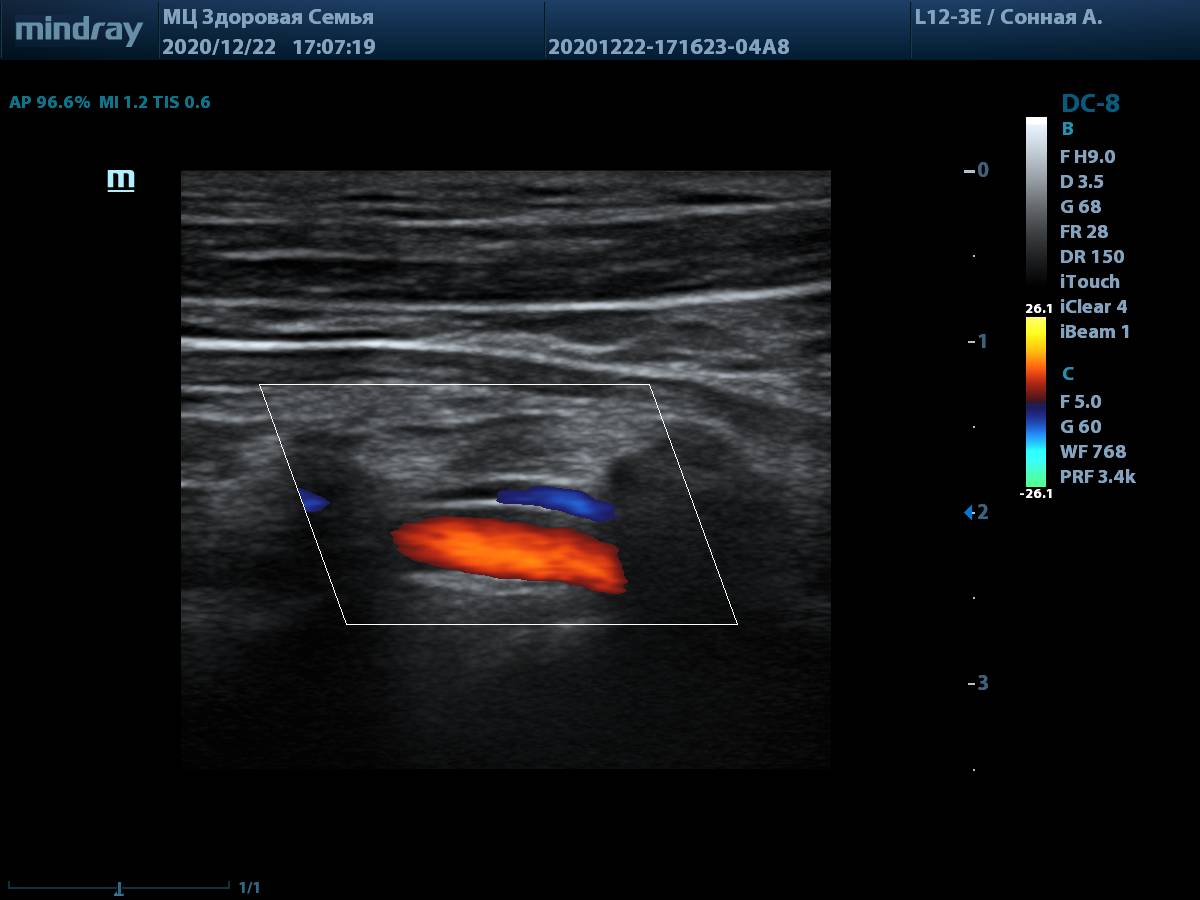

7. Линейный датчик L12-3E, оценка глубоких структур, таких как позвоночная артерия, не вызывает трудностей. Хорошая чувствительность цветового допплера на глубине.

Позвоночная артерия, CFM